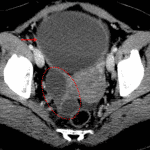

Age: 24

Sex: Female

Indication: Abdominal distension and pain

- Abdomen/Pelvis

- Large, predominantly cystic mass measuring 30 x 30 x 15 cm filling the pelvis and much of the abdomen, which appears to arise from the left ovary

- Several thin internal septations in the upper right aspect of the mass

- The right ovary is separate from this mass with several intraovarian cysts measuring up to 4.8 cm

- Heterogeneous enhancement of the uterus

- No bowel obstruction or hydronephrosis

- Small volume free fluid layering in the anatomic pelvis

Diagnosis

- Cystic ovarian neoplasm (mucinous cystadenoma)

Large predominantly cystic mass appearing to arise from the left ovary with extensive mass effect but no evidence of bowel obstruction or hydronephrosis. The primary differential consideration is a cystic ovarian neoplasm. Recommend gynecology assessment and consideration of MRI for further evaluation.

Cystic right ovarian lesions which can also be further evaluated with MRI.